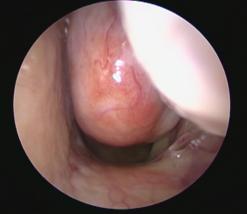

• Image

Computed tomography (CT) of the sinuses showing a spontaneous CSF leak from a right ethmoid sinus skull base defect

Computed tomography (CT) of the sinuses showing a spontaneous CSF leak from a right ethmoid sinus skull base defect involving the lateral lamella of the cribriform plate, repaired endoscopically

Cerebrospinal fluid (CSF) leak and encephaloceles repair: Spinal fluid leaks into the nose may occur spontaneously or as a result of craniofacial trauma. These leaks can usually be repaired endoscopically through the nose to prevent the development of meningitis. We perform these endoscopic repairs by inserting a thin instrument into the nose.